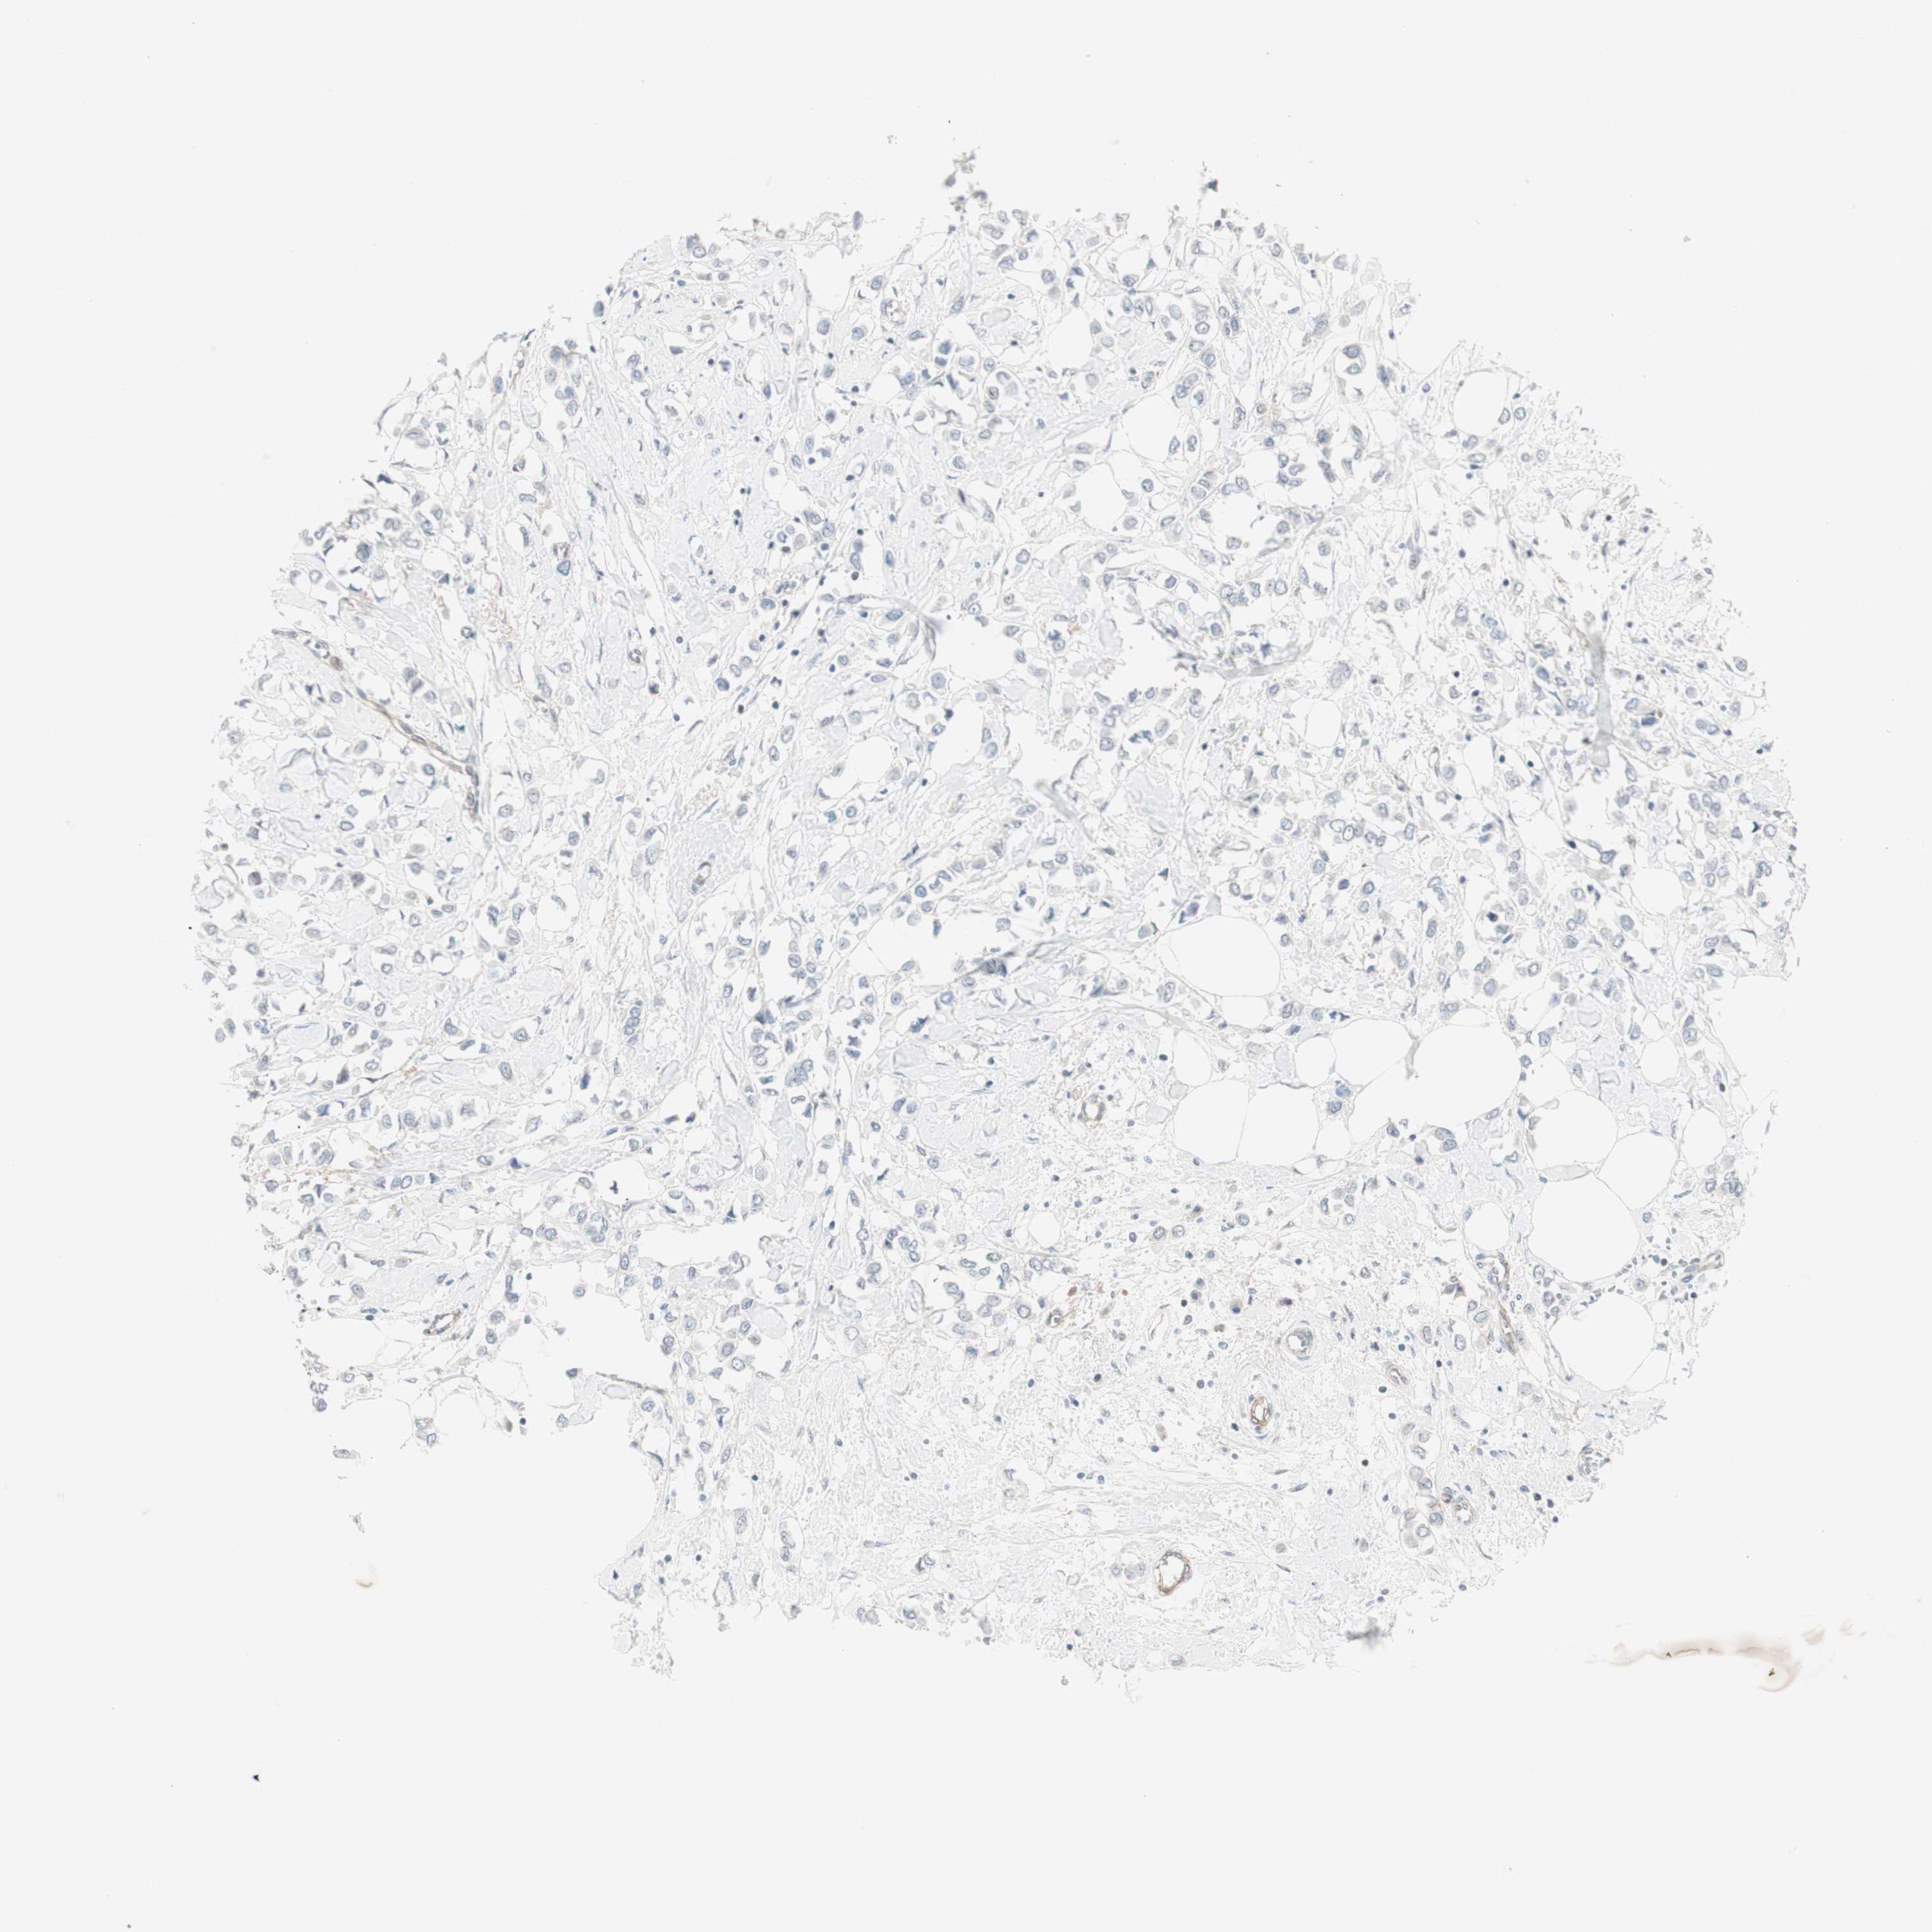

BRCA TCGA BRCA VALIDATION PROTEIN EXPRESSION